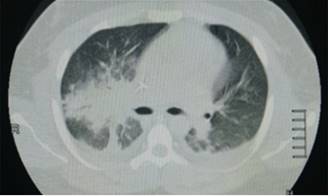

Paciente masculino en segunda década de la vida quien consulta al servicio de urgencia por cuadro clínico de 48 horas de evolución consistente en aumento del trabajo respiratorio e incremento de la clase funcional asociado a malestar general, fiebre no cuantificada y tendencia a la somnolencia con deterioro de los índices de oxigenación, por lo que se decide remitir a cuidados intensivos. Como único antecedente se refiere obesidad e hipertensión. Ingresa a la unidad de cuidados intensivos con tensión arterial de 60/30 mmHg, frecuencia respiratoria de 35 por minuto, frecuencia cardiaca de 150 latidos por minuto con registro en visoscopio sugestivo de fibrilación auricular, febril 39o con Glasgow de 10/15, saturación de 85% con Ventury al 50% con uso de músculos accesorios, por lo que se decide proteger vía aérea previa inducción de secuencia rápida con sedación y relajación, se realiza laringoscopia directa encontrando Cormack-Lehane III, se avanza tubo orotraqueal sin eventualidad1,2 monitoria de la ventilación mecánica, deterioro de propiedades pulmonares mecánicas dinámicas y estáticas con compliance en 28 cm de agua, presión meseta de 18 cm de agua, resistencias de la vía aérea en 6 cm3/litro/segundo, presión de conducción de 11 cm.3,4 Se accede vía central documentándose presiones de fin de lleno subóptimas con resistencias vasculares sistémicas en 450 dinas/superficie corporal/segundo. Información gasométrica con predicción aguda de bajo gasto por aumento del gradiente venoarterial de CO2 y predicción de hipoperfusión tisular por incremento del cociente metabólico anaeróbico, hiperlactatemia y acidemia metabólica importante.5,6 Se realiza electrocardiograma que documenta fibrilación auricular. Reportes de laboratorios de ingreso registrados en la Tabla 1. Se efectúan cultivos de vigilancia y se despliegan terapias tempranas dirigidas por objetivos.7,8 Es llevado a escanografía de tórax que documentan derrames pleurales bilaterales y consolidación más hepatización en el lóbulo medio (Figura 1). Se realiza ecocardiograma Doppler dúplex color transtorácico en virtud de hallazgos electrocardiográficos y marcadores de necrosis miocárdica referidos de ingreso, el cual reporta crecimiento del ventrículo izquierdo con fracción de eyección de 46% sin trastornos de la contractilidad, se descartó miocardiopatía inducida por sepsis con histonas negativas.9,10 Se decide estratificación de riesgo coronario con perfusión miocárdica isonitrilos, la cual revela miocardiopatía dilatada hibernante sin insuficiencia coronaria (Figura 2). Evoluciona con alto requerimiento de vasoactivos e inotrópicos con persistencia de falla circulatoria y marcadores de actividad inflamatoria en gases por hipercloremia e incremento de carboxihemoglobina, por lo que se decide escalamiento antibiótico.11 Presenta deterioro de la oxigenación y de la ventilación con deterioro de la mecánica ventilatoria, razón por la que se inicia protección pulmonar y ajuste de presión positiva por bucle presión volumen, meseta y fracción inspirada de oxígeno.12-14 Reportes de cultivos de vía aérea, hemocultivos y orina negativos; reporte de hisopado rectal documenta enterobacteria con resistencia extendida productora de muro péptidos e inductora de anhidromuropéptido codificado del gen C (AMPc), además mecanismos de resistencia nuclear por topoisomerasa IV y porción polirribosomal 50 s dando continuidad a carbapenémicos.15 Persiste fibrilación auricular e injuria pulmonar severa, por lo que se solicitan marcadores de actividad fibrinolítica con dímero D en 3.5 mg/dL. Es llevado a perfusión pulmonar documentándose defectos segmentarios de distribución vascular en los segmentos basales y laterales del lóbulo inferior izquierdo, así como segmento anterior del lóbulo superior ipsilateral y en segmento anterior del lóbulo superior derecho compatible con alta probabilidad de tromboembolismo pulmonar por criterios prospective investigative of study acute pulmonary embolism diagnosis (PISAPED) (Figura 3).16 Se documenta deficiencia de antitrombina III y mutación del factor V de Leiden en el escenario de estudios de hipercoagulabilidad y estudios autoinmunes negativos, los reportes se registran en la Tabla 2. Ante la persistencia de fibrilación auricular y choque obstructivo se decide trombólisis con lo cual se logra estabilidad hemodinámica y disminución en los parámetros ventilatorios. Evoluciona favorablemente con tolerancia a la suspensión del soporte farmacológico, se pasa a asa cerrada en asistencia proporcional con recuperación importante de la mecánica ventilatoria compliance total de 90 cm de agua, resistencias de 4 cm/litro/segundo, presión elástica alveolar de fin de espiración normal, elastancia de 20 cm de agua con trabajo respiratorio impuesto de 0.3 Jouls por litro, por lo que se realiza prueba única diaria con tubo en t sin predictores de falla de extubación, y se decide liberación de la ventilación mecánica.17,18 Es trasladado a piso para manejo por medicina interna y hematología.